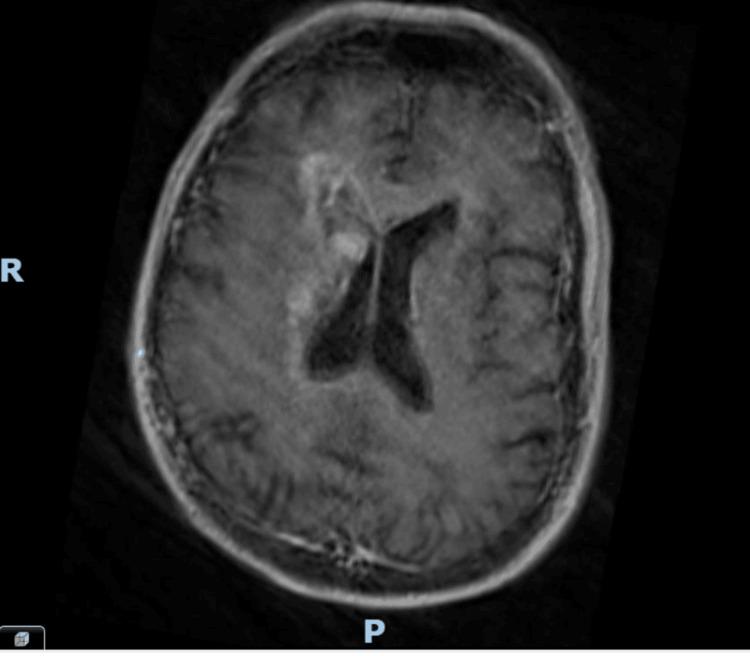

Cognitive impairment in the elderly is often attributed to neurodegenerative processes such as dementia or delirium. However, in some cases, structural brain lesions, including malignancies like glioblastoma and lymphomas, can present similarly. This case report is of a 79-year-old male with progressive cognitive decline who was initially suspected to have dementia but was later found to have a brain mass. The absence of focal neurological deficits and a normal initial CT scan delayed the recognition of an underlying malignancy. An MRI ultimately revealed a lesion concerning glioblastoma or primary central nervous system lymphoma (PCNSL). Given the patient's frailty, the neuro-oncology multidisciplinary team (MDT) recommended best supportive care rather than an invasive biopsy. This case underscores the importance of thorough assessment and neuroimaging in cases of unexplained cognitive decline and highlights the diagnostic pitfalls that can lead to misdiagnosis.

老年人的认知障碍通常归因于神经退行性过程,如痴呆或谵妄。然而,在某些情况下,包括胶质母细胞瘤和淋巴瘤等恶性肿瘤在内的脑结构病变也可能表现出类似症状。本病例报告的是一名79岁男性,其认知功能进行性下降,最初被怀疑患有痴呆,但后来发现有脑肿块。由于缺乏局灶性神经功能缺损且初始CT扫描正常,导致对潜在恶性肿瘤的识别延迟。最终MRI显示出一个可疑的胶质母细胞瘤或原发性中枢神经系统淋巴瘤(PCNSL)病变。鉴于患者身体虚弱,神经肿瘤多学科团队(MDT)建议采取最佳支持治疗,而非进行侵入性活检。该病例强调了在不明原因认知下降病例中进行全面评估和神经影像学检查的重要性,并突出了可能导致误诊的诊断陷阱。